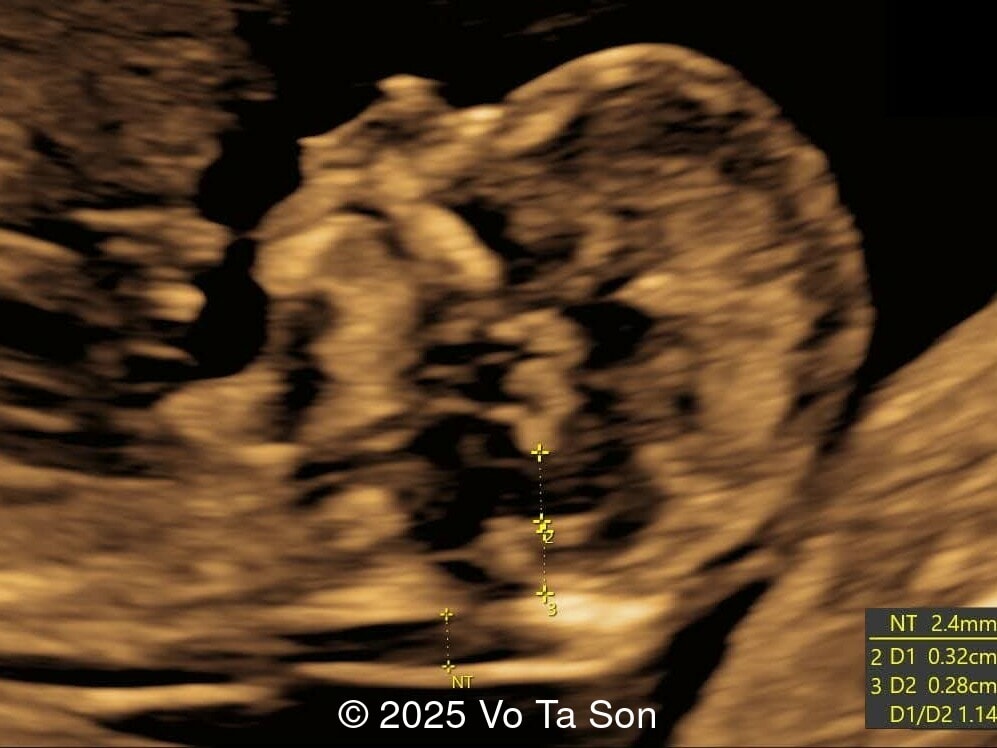

A woman underwent routine prenatal screening at 13 weeks. The non-invasive prenatal test (NIPT) showed low risk for common aneuploidies including trisomy 21, 18, and 13. However, first-trimester anomaly scan revealed multiple fetal anomalies.

Please describe the abnormalities and provide a syndromic diagnosis that best fits the presentation.